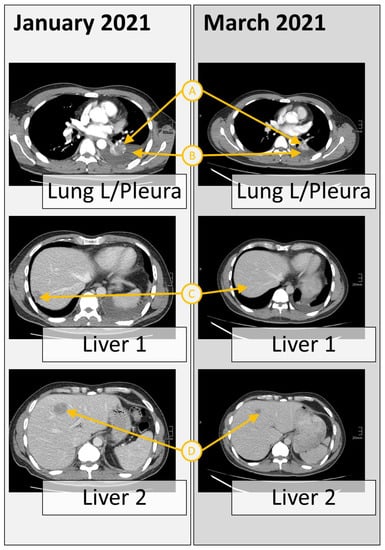

In January 2021, after 9 months of initial first-line treatment with osimertinib, a second molecular analysis was performed from the progredient hepatic metastases, which confirmed the original EGFR and TP53 mutations and revealed additional deletions in TP53, NRAS, BRCA2, ARAF, a low-level EGFR, and a focal MET amplification. As MET-amplified NSCLC has been reported as sensitive to the small-molecule TKI crizotinib in multiple studies [5,19], the patient started to receive the combined treatment of osimertinib (80 mg) with crizotinib (250 mg). Six weeks later (March 2021), the patient showed partial remission in both lung and hepatic sites and regression in pleural effusion and cervical lymph nodes (Figure 2). As side effects, slight cutaneous toxicity was observed; besides this, the patient showed a good appetite and stable weight as part of a routine health status assessment in July 2021.

Figure 2. Response to the combined treatment of osimertinib with crizotinib of multiple sections. Computer tomography scan from the chest and liver sections at the time of tumor progression after osimertinib, revealing multiple metastases (January 2021), and after 6 weeks of therapy with crizotinib plus osimertinib, revealing partial remission in both lung and hepatic sites. The reduction can be seen in tumor size (A), pleural effusions (B), and the liver metastatic sites (C and D).